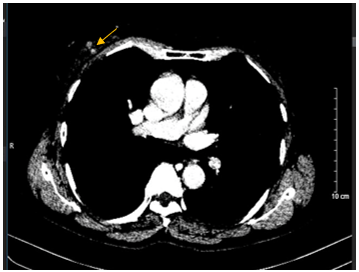

- Cắt lớp vi tính lồng ngực: Không phát hiện tổn thương tổn thương phổi bất thường. Vú phải có nốt ngấm thuốc vị trí 12 giờ-13 giờ, kích thước 10x12mm.

Hình 5: Hình ảnh cắt lớp vi tính lồng ngực: Hình ảnh vú phải có nốt ngấm thuốc vị trí 12 giờ -13 giờ, kích thước 10x12mm (mũi tên màu vàng).